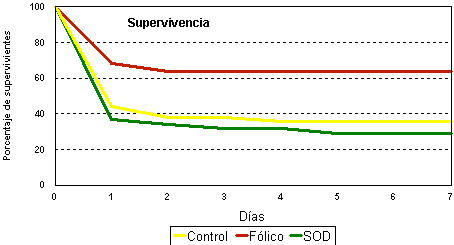

| 4 | Estudio del defecto de fármacos antioxidantes sobre la tasa regenerativa basal en el hígado sometido a isquemia normotérmica. El ácido fólico y la súperoxido dismutasa se demuestran efectivos; el alopurinol no produce ningún efecto. |

| 8 | El ácido fólico y la superóxido dismutasa mejoran el funcionalismo hepático en el hígado sometido a isquemia intermitente |